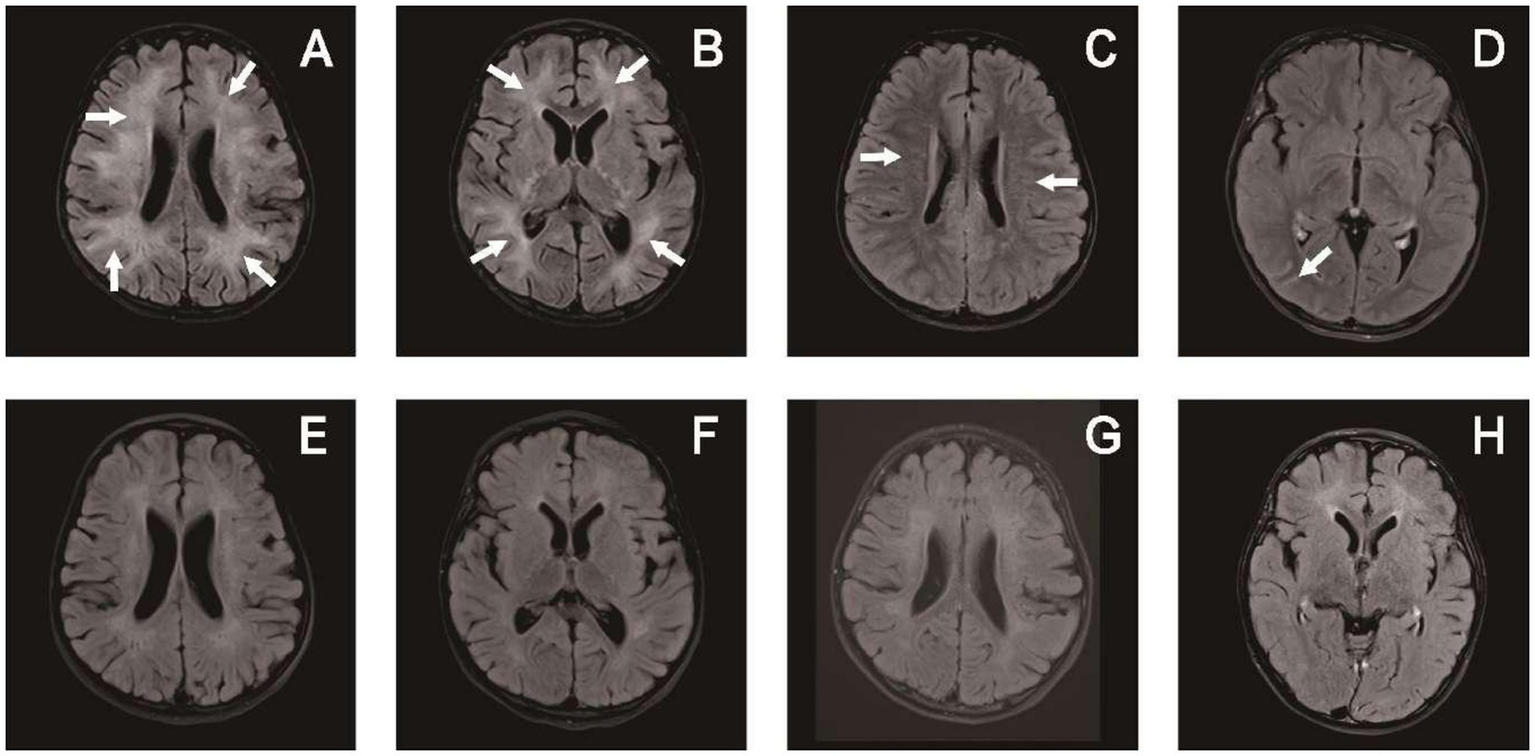

A head MRI scan was completed in 14 patients and a spinal cord MRI scan was completed in 10 patients. Eight of these scans showed abnormalities on head MRI, three reflected head and spinal cord MRI abnormalities, and one manifested head and optic nerve MRI abnormalities. Eight patients also exhibited enhanced shadows. The heads of the children chiefly showed cortical and subcortical white matter involvement, with 1–10 sites of involvement. Bilateral lesions were the most common (n = 8) and all were asymmetric, numbering twice that of the unilateral lesions (n = 4). The involved sites included the frontal lobe (n = 9), parietal lobe (n = 8), occipital lobe (n = 8), temporal lobe (n = 6), thalamus (n = 5), periventricular white matter (n = 4), cerebellum (n = 4), brain stem (n = 3), basal ganglia (n = 3), corpus callosum (n = 3), caudate nucleus (n = 1) and hippocampus (n = 1). Only three patients presented with spinal cord lesions: one comprised thoracic-lumbar spinal cord T1-L1, one involved the cervical spinal cord C3-C6, and one encompassed extensive spinal cord lesions. Lesions diminished or disappeared after treatment in the 11 patients with imaging abnormalities, and four children had complete disappearance of the lesion on MRI reexamination, occurring 2 months to 2 years and 3 months after disease onset (Figures 3, 4).

Figure 4

Brain MRI of patient 6 in Table 1: upon admission (A–D) and 3 months later (E–H). (A,B) T2-hyperintense lesions in the white matter of bilateral cerebral hemispheres. (C) Periventricular radial linear enhancement. (D) Enhanced shadow of occipital lobe sulci. (E–H) Follow-up images of improved T2 lesions and enhancement.